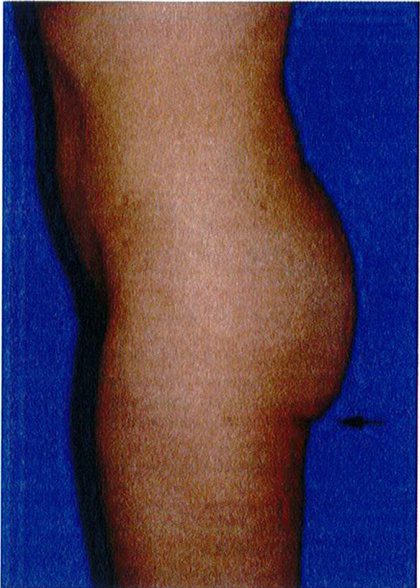

Phân loại sa mông

Phân loại này được áp dụng khi có vùng da sa xuống dưới nếp lắn mông và chúng được chia thành 3 giai đoạn I, II, III (Hình 28).

Giai đoạn I

GĐ I rất giống với phân loại không sa – lớp C; tuy nhiên, một phần thể tích mông và da sa xuống dưới nếp lằn mông (mức độ ít). Khi nhìn nghiêng, sẽ phát hiện 1 nếp lằn rõ nằm ngang. Trong những trường hợp này, chỉ cần làm đầy mông mà không cần nâng mông trên.

Giai đoạn II

Bệnh nhân ở giai đoạn II, nếp lằn mông vẫn còn nhìn thấy nhưng có tổ chức da sa xuống dưới nếp lắn. Trong khi nếp lắn mông ở giai đoạn I còn nằm ngang thì giai đoạn Il có góc cạnh hơn. Cụ thể, thường có một độ lõm nhất định ở phần trên của vùng mông dưới

Bệnh nhân ở giai đoạn này có phần da chùng nhiều nhất, xuống dưới nếp lằn mông khi nhìn từ phía

bên. Nếp lằn này mở rộng về phía mặt trong đùi, và góc tạo bởi chúng và đường liên mông thường lớn hơn 30°. Giai đoạn này cũng được mô tả bởi chỗ lõm ở phân dưới của khu vực trung tâm (hình 28). Các vết rạn da xuất hiện chủ yếu ở vùng điểm B, và da có độ đàn hồi kém với các vết rạn rải rác. Điều trị bệnh nhân ở giai đoạn này cần thực hiện nâng mông trên, cắt vùng da thừa dưới nếp lằn mông và làm đầy mông. Trong các thủ thuật này, có thể thực hiện 1 trong 3 trước đều được.

Ptosis Grade I 0°-10°: Sa mông GĐ 1 0°-10° Ptosis Grade II 10º-30º Ptosis Grade III 30° or greater: Sa mông GĐ III 30° hoặc hơn

Ptosis Grade II 10°- 30°

Hình. 28. Giai đoạn I, II, III của bệnh nhân có tình trạng sa mông. Ở giai đoạn I, góc tạo bởi nếp da nhỏ hơn 10 độ. Ở giai đoạn II, focs này rơi vào khoảng từ 10- 30 độ. Còn ở giai đoan III, góc tao bởi nếp da lớn hơn 30 đô.